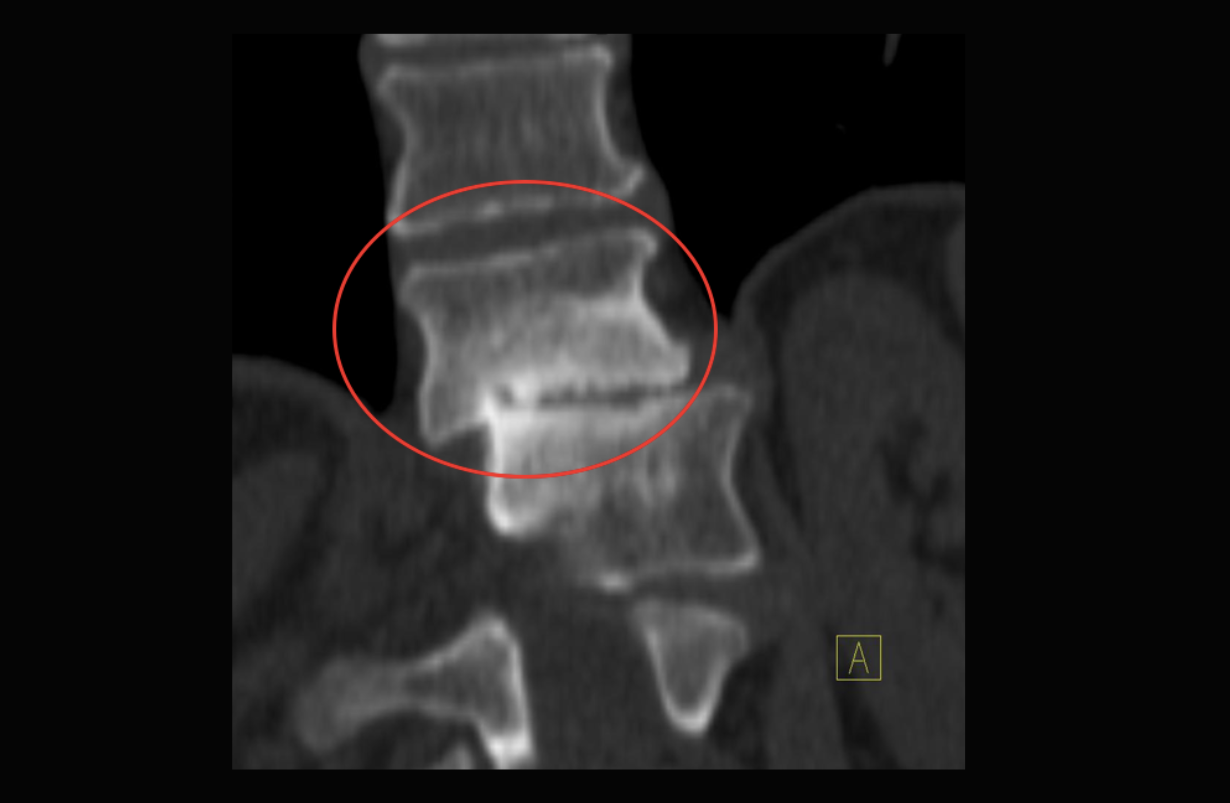

Anterolisthesis

Forward sliding of one vertebra on the one below it: Grade I - 1-25% Grade II - 25 - 50% Grade III - 50 - 75% Grade IV - 75 -100% The vast majority are Grade I, but even that can be significant if there is also a bulging disc, arthritis, or other factors that narrow the central spinal canal or the narrow neuroforamina through which nerve roots pass on their way to the legs or arms.